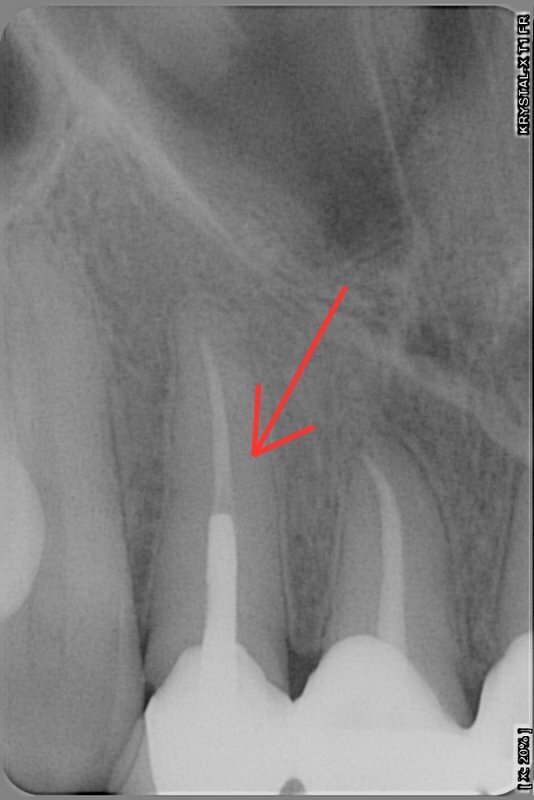

Большинство людей боятся стоматологов. В том числе и я. Я помню свой первый визит к такому врачу. Не могу сказать, что я боялась. Я волновалась из-за результата. Все прошло более менее хорошо. Так мне показалось сначала. Но через какое-то время начались осложнения, с которыми я не могла справиться лет 5. Подобный опыт у меня был не единственный. Мне нужно было удалить нерв из зуба, который не болел для дальнейшего лечения. Удалили. Было больно, но я справилась. Потом положили временную пломбу. Зуб болел месяц. Врач не понимал почему возникает боль и в итоге сказал, что со временем пройдет и запломбировал зуб окончательно. Я видела рентгеновские снимки. Мне казалось, что канал не до конца закрыт. Я говорила это врачу, он уверял меня, что так и надо.

Я год ходила и ждала, когда же успокоится зуб. Он успокоился когда другой стоматолог вскрыл его и доделал канал.